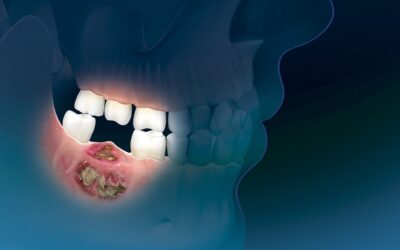

Οδοντογενείς Όγκοι των Γνάθων

Οι οδοντογενείς όγκοι αποτελούν μία ετερογενή ομάδα σπάνιων όγκων οδοντογενούς προέλευσης (<1% των όγκων της στοματογναθικής περιοχής), οι οποίοι εμφανίζουν διαφορές ως προς τα κλινικά χαρακτηριστικά, την ιστολογική εικόνα, τη βιολογική συμπεριφορά και την...